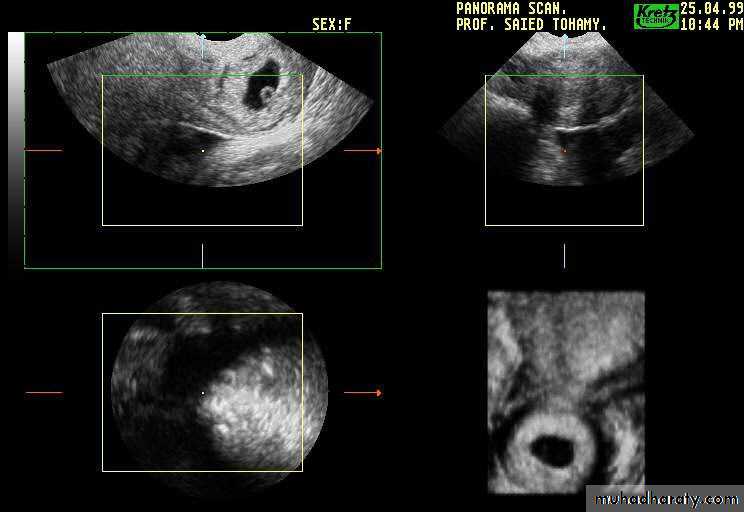

Ultrasound features of ectopic pregnancy:

• The US finding of an extra-uterine sac with embryo is the most reliable diagnosis of EP• An empty ectopic sac or a heterogeneous adnexial mass is a more common US feature

• The presence of fluid in the pouch of doughlas is a non-specific sign of EP

• In 20-30per cent of EP, pseudo-gestational sac is seen as a small, centrally located endometrial fluid collection surrounded by a single echogenic rim of endometrial tissue undergoing decidual reaction